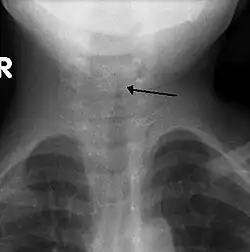

The steeple sign as seen on an AP neck X-ray of a child with croup

A frontal X-ray of the neck is not routinely performed,[4] but if it is done, it may show a characteristic narrowing of the trachea, called the steeple sign, because of the subglottic stenosis, which resembles a steeple in shape. The steeple sign is suggestive of the diagnosis, but is absent in half of cases.[12]